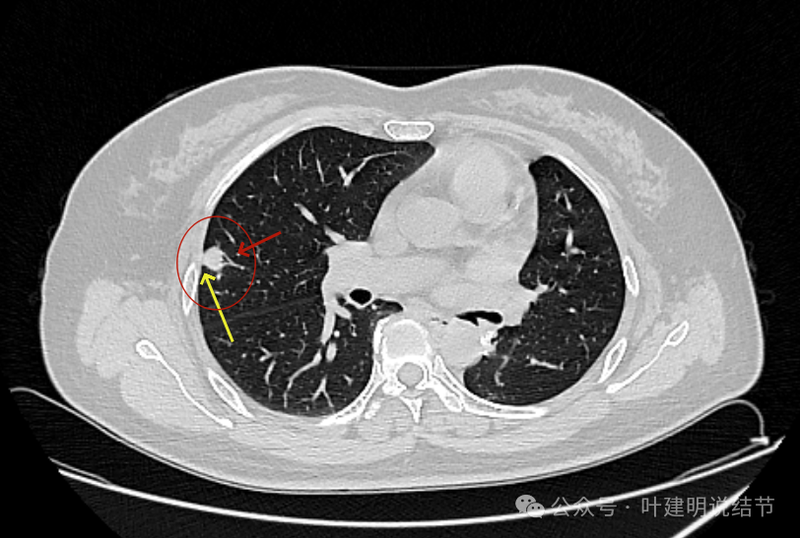

靠着水平理解 ,病灶缺乏收缩力。

叶裂于此处略有增厚。

2023年2月时右上叶同一处没有明显病灶。

右上前后相差15个月的对比。